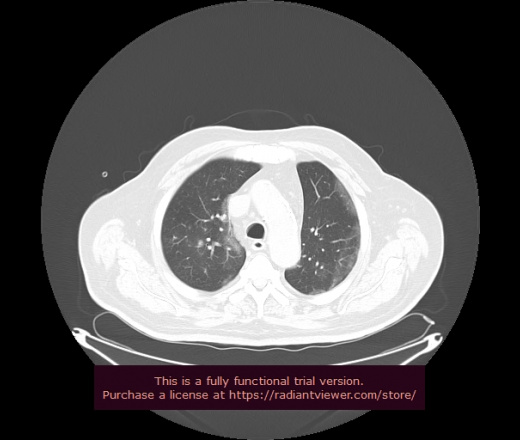

Уважаемые коллеги, если имеется интерес, сможете ли Вы спрогнозировать дальнейшее +-одинаковое течение процесса у 4 данных разных пациентов? Зацепиться где-то можно очень просто, где-то нельзя.